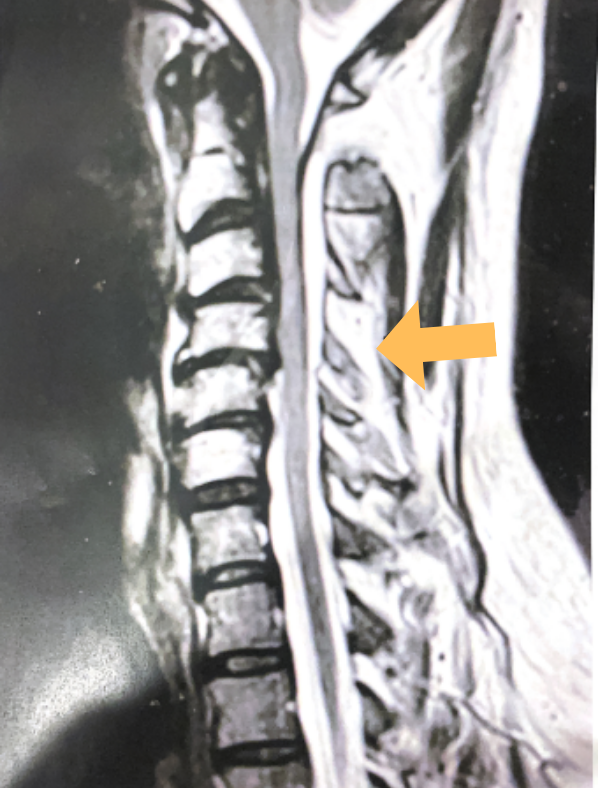

Central Cord Syndrome

Author: Yusef Imani M.D., F.A.A.N.S., Read More!